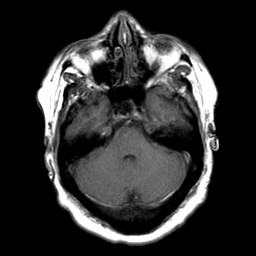

Cerebral hemorrhage, MR Study mr-t1 -- Slice #7

[Home][Help][Clinical] Slice 7